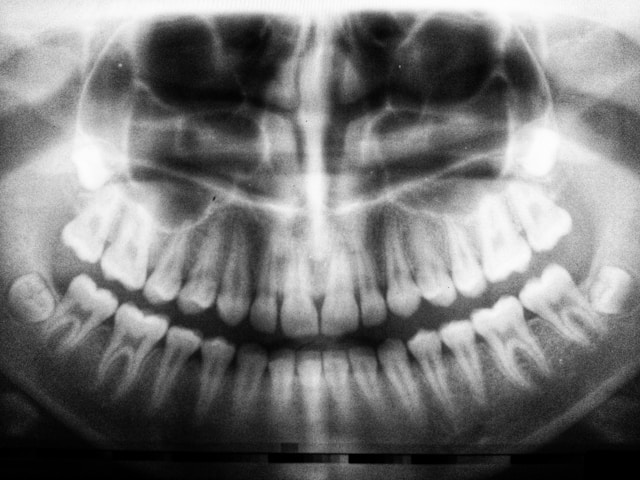

muelas del juicio

Muelas del juicio: qué son, cuándo salen y cuándo hay que extraerlas

Las últimas piezas dentales en brotar de toda nuestra dentadura son las muelas del juicio. Su erupción inicia entre la adolescencia y la adultez joven, no siempre ocasiona molestias o problemas, pero de ser así, deberán extraerse. Aquí te explicamos sobre este tema y cuándo acudir a tu dentista.

Las muelas del juicio, conocidas en odontología como los terceros molares, son cuatro, dos en el maxilar y dos en la mandíbula. Se encuentran ubicadas al fondo de la boca.